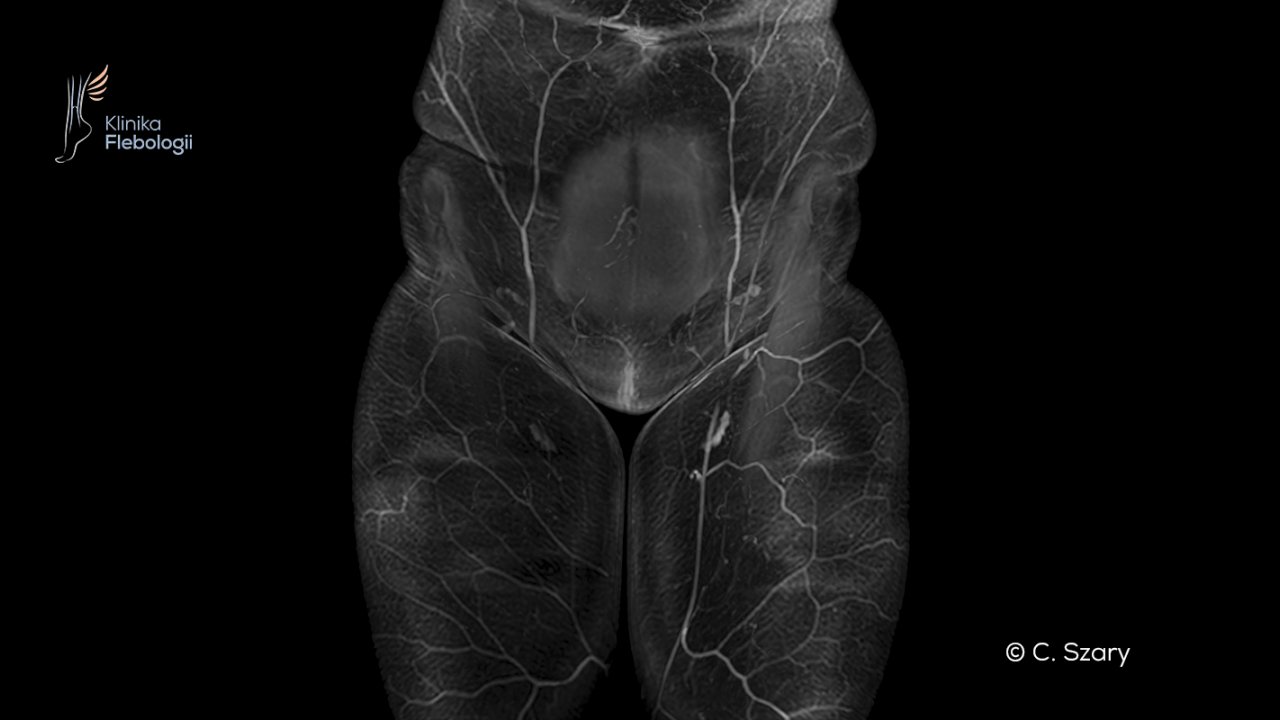

Wenografia rezonansu magnetycznego (MRV) wykonywana współcześnie umożliwia nam dynamiczne obrazowanie żył. Współczesne badania wenograficzne dorównują jakością i rozdzielczością badaniom tomograficznym. W czasie badania wykorzystywane są nowoczesne środki kontrastowe, które aplikuje się drogą dożylną w niewielkich ilościach.  Badania wyłącznie techniką bezkontrastową dostarczają dużo mniej informacji, stąd są przez nasz zespół praktycznie niewykonywane. Zespół Kliniki Flebologii wykonuje tego typu badania w pracowni rezonansu magnetycznego Centrum Medycyny Sportowej na wysokopolowym skanerze firmy Philips (Ingenia 3T). Obrazy otrzymywane na aparacie 3T przewyższają jakością i dokładnością badania z aparatów 1,5 Teslowych. Badanie trwa około 35-45 minut w zależności od zastosowanego protokołu. Wykonywane jest na czczo (badania w godzinach rannych) lub 6-8h po posiłku (badania w godzinach popołudnowych).

Wenografia to nowoczesny sposób obrazowania układu żylnego. Należy do pośrednich technik obrazowania układu żylnego, wykorzystujących zjawisko krążenia krwi, które może być śledzone po podaniu odpowiedniego środka kontrastowego (wenografia kontrastowa) lub bez użycia kontrastu, techniką bezkontrastową. Technika bezkontrastowa w praktyce jest mało przydatna i nie jest wykorzystywana w kwalifikacji pacjenta do procedur zabiegowych.

W Klinice Flebologii w diagnostyce obrazowej układu żylnego stosowana jest technika wenografii rezonansu magnetycznego (MRV) z podaniem bezpiecznych gadolinowych środków kontrastowych. Jest to badanie wyjątkowo mało inwazyjne, dokładne, dostarczające zarazem dużo dodatkowych informacji o mechanizmie chorobowym.